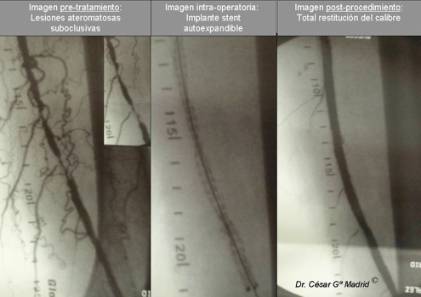

La cirugía vascular arterial ofrece una aportación imprescindible en el salvamento de extremidades mediante la combinación de sofisticadas técnicas de revascularización como son los diferentes tipos de by-pass y procedimientos endovasculares minimamente invasivas.